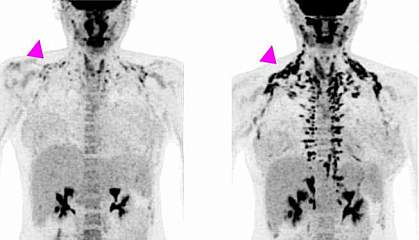

Researchers Study Cold Exposure for Cancer Therapy

New Research: Cold Exposure for Cancer and HealthDiscover how mild cold exposure activates brown fat to slow cancer growth by reducing the glucose that cancer cells need. Walking or rucking outdoor...